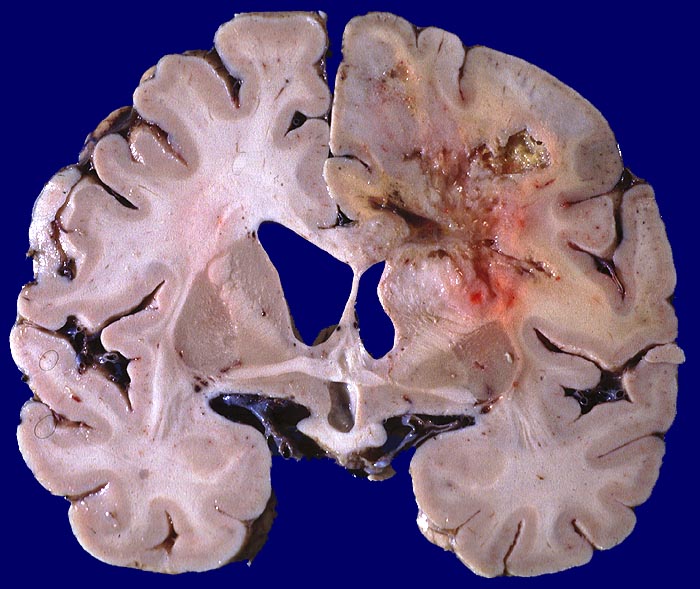

Glioblastoma multiforme

Hirn parietal

Bunte Tumorschnittfläche im parietalen Marklager mit ausgedehnten zentralen Nekrosen und unscharfer Begrenzung.

Frontoparietal zystische Nekrosehöhle Durchmesser 6cm. Infiltration von Nc. caudatus, Corpus callosum und Capsula interna rechts.

Hirntumor bekannt seit einem Jahr

Makroskopie